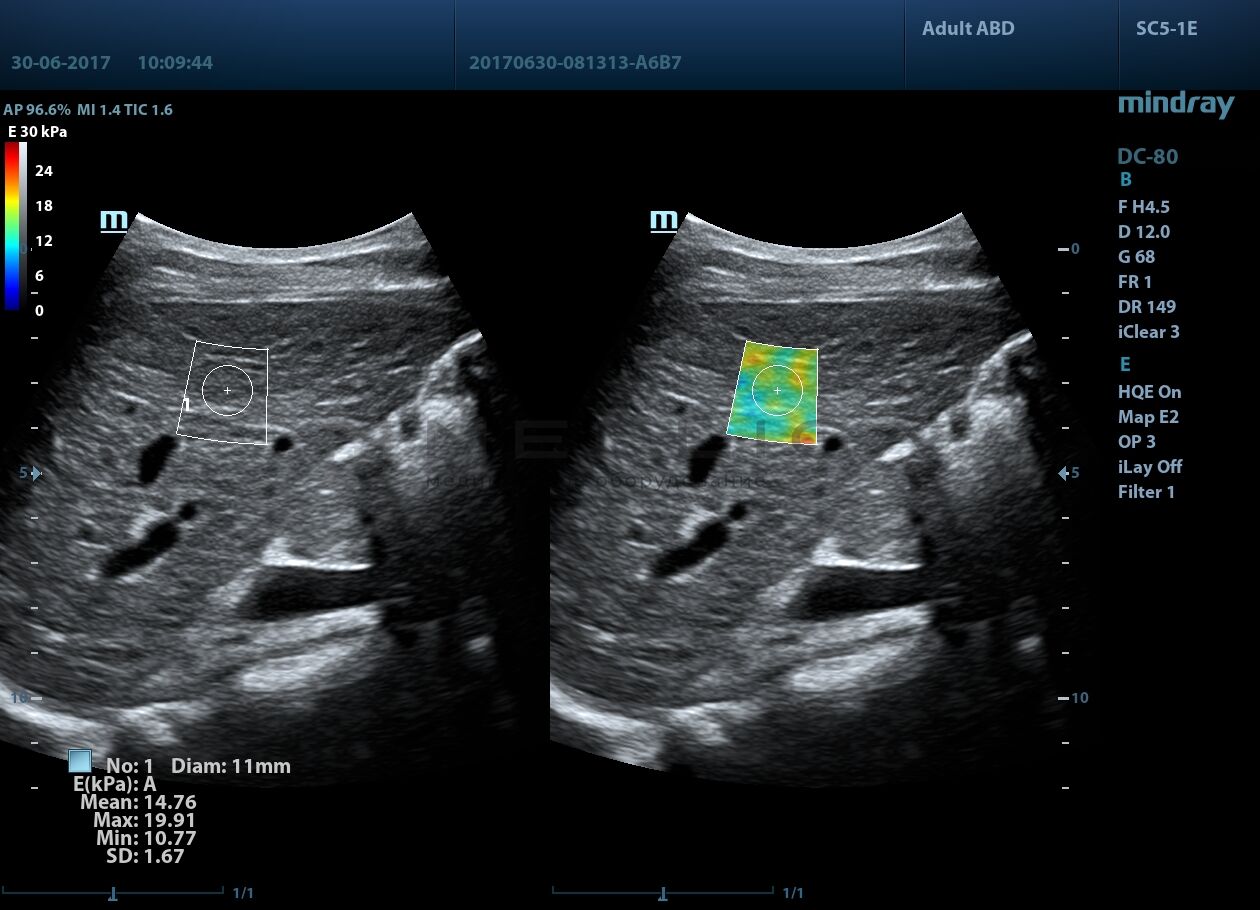

STE (Sound Touch Elastography)

STE интегрирована с эксклюзивной технологией Ultra-Wide Beam Tracking от Mindray для двумерной эластографии сдвиговой волной в реальном времени. Специализированные измерительные инструменты позволяют проводить количественный анализ модуля упругости с высокой точностью.

- на линейных датчиках

- на конвексных датчиках